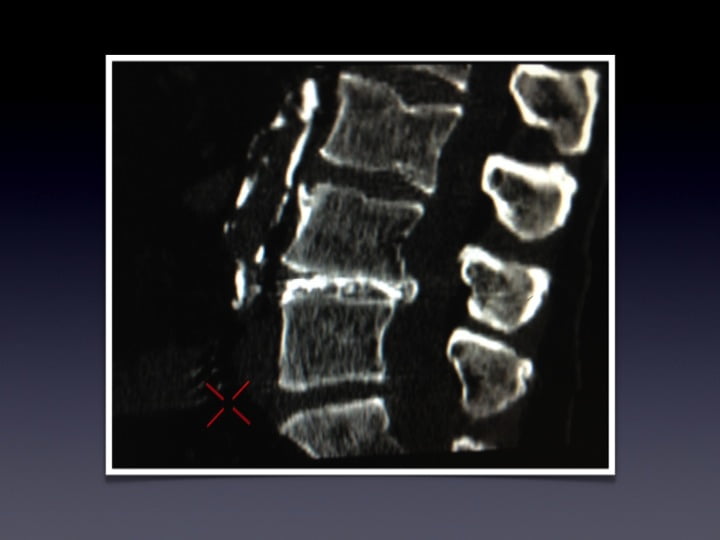

• Vertebroplastie et burst A2

• Vertebroplastie et kyphoplastie: radiation dose to radiologist

• Emanation de PMMA

• Vertebroplasty and schmorl hernia

• Vertébroplastie et arthrodèse rachidienne

• Ostéoplastie et vissage percutanné

• Extraction de fuites de ciment

• Kyphoplastie-vertebroplastie